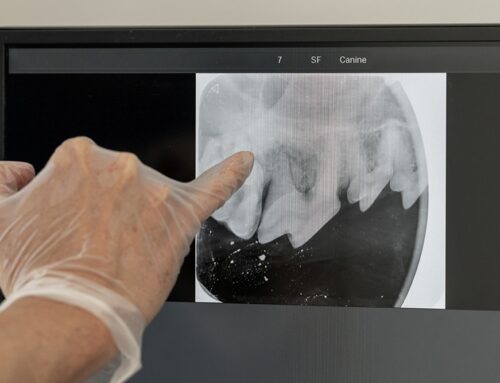

Dental X-rays for pets reveal hidden problems beneath the gum line, including tooth root infections and bone loss that aren’t visible during visual examination alone. Blood testing evaluates overall health status and screens for viral infections that may contribute to immune dysfunction.